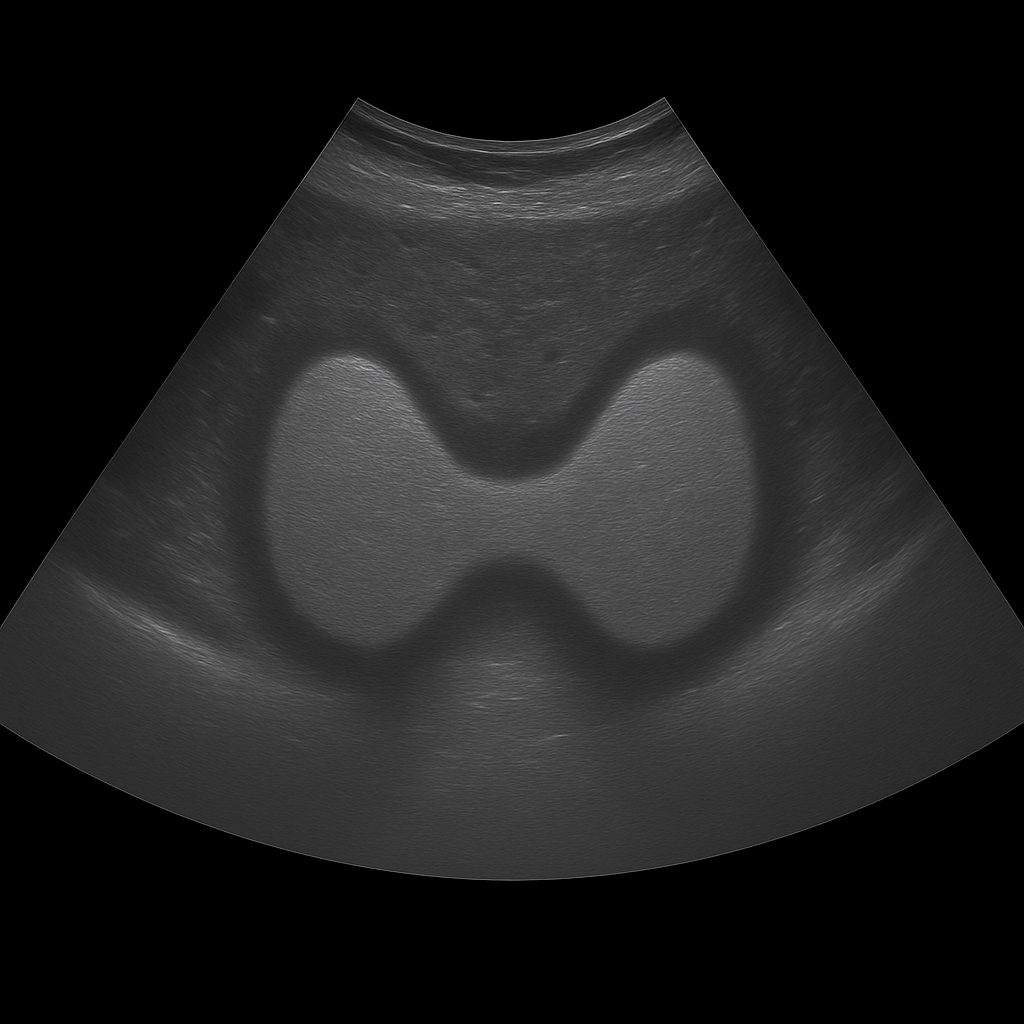

MRI Prostate

Magnetic resonance imaging

- MRI of the prostate – with IV contrast if needed.

- Detects prostate cancer at an early stage.

- Distinguishes benign from malignant changes.

- Shows enlargement and inflammation of the prostate.